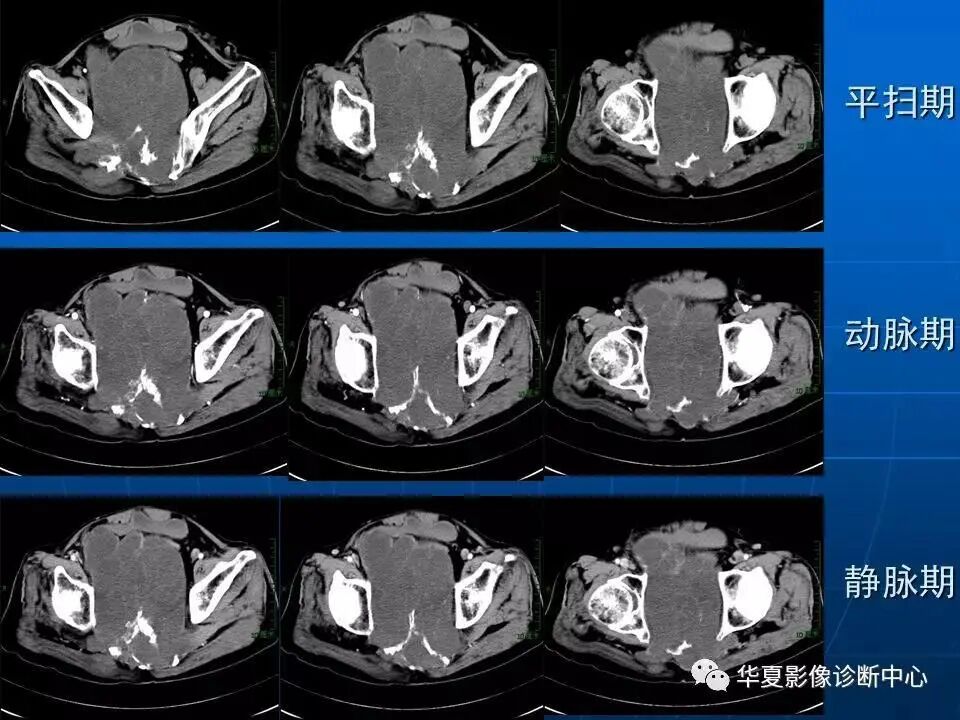

二、患者男,51岁,骶尾部脊索瘤,2022年5月23日行重离子治疗。

治疗前2022年5月6日 治疗后2024年8月12日